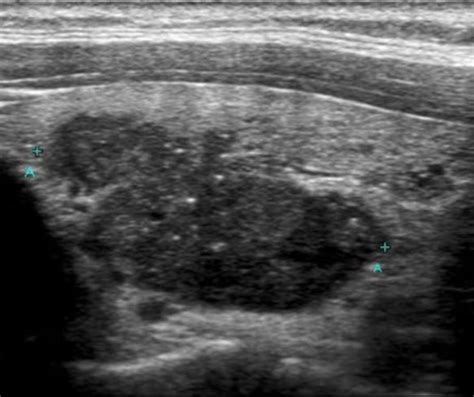

Now, let’s switch gears and talk about Papillary Thyroid Cancer (PTC). It’s the most common type of thyroid cancer, accounting for a significant number of thyroid cancer diagnoses. Thyroid cancer occurs when cells in the thyroid gland grow out of control. The thyroid gland, located in the neck, produces hormones that regulate metabolism and other critical body functions. PTC usually originates in the thyroid gland’s follicular cells. There are different types of thyroid cancer, but PTC is the most frequently diagnosed. Early detection is very important. PTC often develops slowly, which means it may not show obvious symptoms in its early stages. This makes regular check-ups with your doctor essential. If PTC is detected early, the treatment is typically successful. However, in advanced stages, it can spread to other parts of the body. Treatment usually includes surgery to remove the thyroid gland, followed by radioactive iodine therapy. There are also targeted therapies and other treatments that may be used depending on the cancer’s stage and other factors. Understanding the basics of PTC can help you navigate the diagnostic process. Being aware of the risks and recognizing the early symptoms is critical to finding it early. Knowledge is power. If you have concerns, it’s essential to consult with healthcare professionals. They can conduct tests and provide you with an accurate diagnosis and treatment plan. Regular self-exams and awareness of your body are also crucial in early detection.

Papillary Thyroid Cancer has several distinct characteristics. The cancer cells often resemble normal thyroid cells. When observed under a microscope, these cells show unique features that help doctors diagnose the disease. One key characteristic of PTC is its tendency to spread to nearby lymph nodes in the neck. This means the cancer cells can move beyond the thyroid gland and impact the lymph nodes. Although the cancer may spread, it’s often a slow-growing cancer, making it possible to treat it effectively. PTC also has a good prognosis, particularly when diagnosed and treated early. Survival rates are generally high. However, certain factors may impact the prognosis, such as the size of the tumor, its spread to other areas, and the patient’s age and overall health. Understanding the nature of PTC helps in developing treatment strategies and support. There’s a lot of research focused on improving treatment options and improving outcomes. Knowing the characteristics of PTC is very important for patients and their families. It is also important for healthcare providers to develop tailored treatment plans. This means that doctors consider each patient’s situation and create a plan suited to their specific needs. This patient-centered approach is central to modern cancer care.